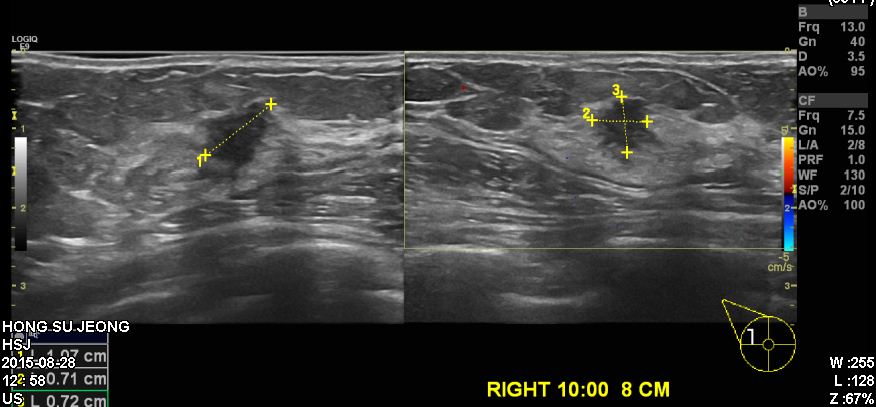

건강검진상 이상소견으로 내원하신 60대 여성분으로  우측 10시 방향에서 8cm 떨어진 거리에 의심스러운 혹 조직검사 시행하여 우측 침윤성 유관암 진단 되었습니다.